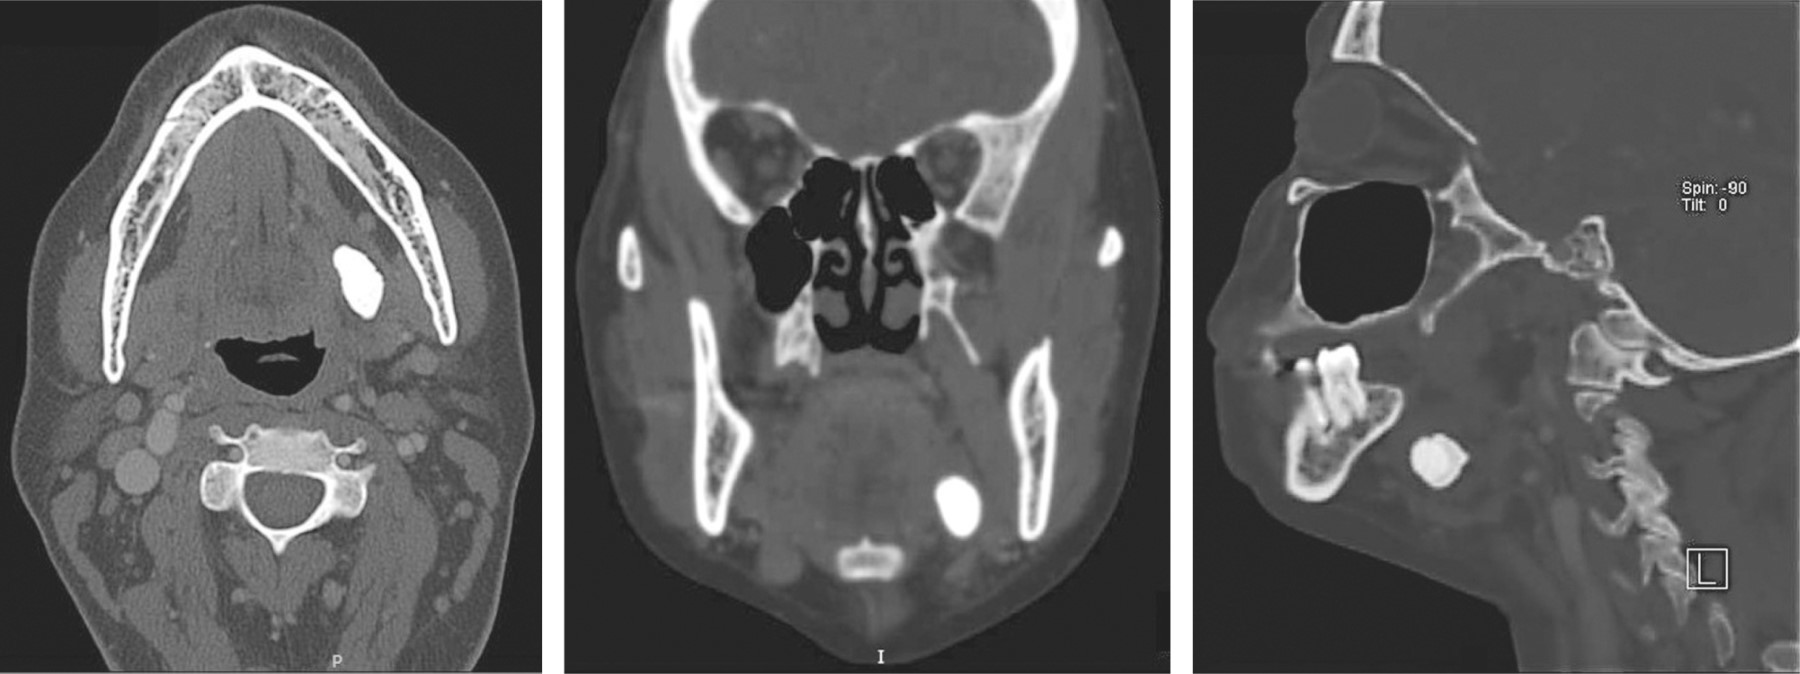

Introduction: Küttner's tumor or chronic sclerosing sialadenitis (CSS) is a rare disease of the major salivary glands. It is characterized by an increase in volume, usually unilateral, although its presence has also been reported in minor salivary glands with or without a relationship with IgG4 disease, producing a fibroinflammatory infiltration in the interlobular septa, but its architecture is preserved and in some cases the presence of stones and positive IgG4 cells. Material and methods: a 44-year-old female patient with tomographic findings of calcification of the left submandibular glands, for which surgical excision of the gland was performed, obtaining a histopathological diagnosis of Küttner's tumor. Results: bimonthly follow-up of the patient continues, currently without the presence of alterations in relation to IgG4 disease. Conclusions: Küttner's tumor or chronic sclerosing sialadenitis (CSS) can sometimes be the initial or only finding of IgG4 disease. The timely diagnosis or the importance of ruling out IgG4 disease is due to all the autoimmune diseases related to it or its possible complications.

Figure 2